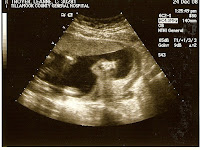

Baby Troyer Ultrasound Pics!

So we have our first pics of our baby!!! We are 11 weeks and 1 day, the doctor said everything went well for our appointment and everything looks good and healthy. :)

Such a relief and an answer to prayer.

It was great the baby was moving around like crazy(hard to believe I can't feel it yet). It even turned around and looked at us and waved! It was so precious!

Now we are two months away from founding out the sex...so this idea we've had for 3 years we finally get to do...we will have the doctor write down what the baby is and we will go to the store and pick out a boy/girl outfit, have the cashier put the correct outfit in a giftbox and we will take it home and open it Christmas morning.

After seeing this little baby yesterday...it just made me feel so calm, at peace, full of joy, and thankfulness for God and His precious gift to us. We actually get to do all the things we said we'd always do. It makes me feel so blessed, and just happy! We have a 16 week appt the monday before Thanksgiving and on december 22 we get to find out the sex(well three days later). :)

So here are our first pics of our little sweetpea, we are so in love and so happy...God is so good!